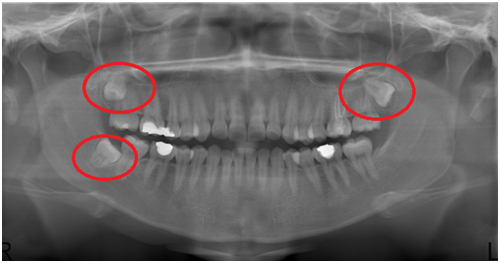

+ Yirmi yaş dişleri ne zaman çekilmelidir?

5) Kist oluşumu: 20 yaş dişleri tam olarak gömülü oldukları veya kısmen gömülü oldukları durumlarda bazı hastalarda kist oluşumuna sebep olabilmektedirler. Bu durum muayene esnasında hekiminizin çekeceği panoramik röntgenle teşhis edilebilmektedir.